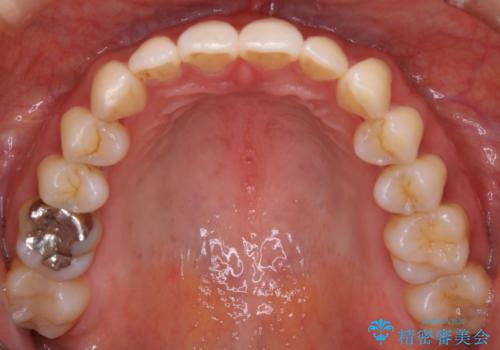

【非抜歯】歯を抜かなくても短期間でキレイな歯並びに

- 30代 女性

- マウスピース(インビザライン)

- 1年6ヶ月